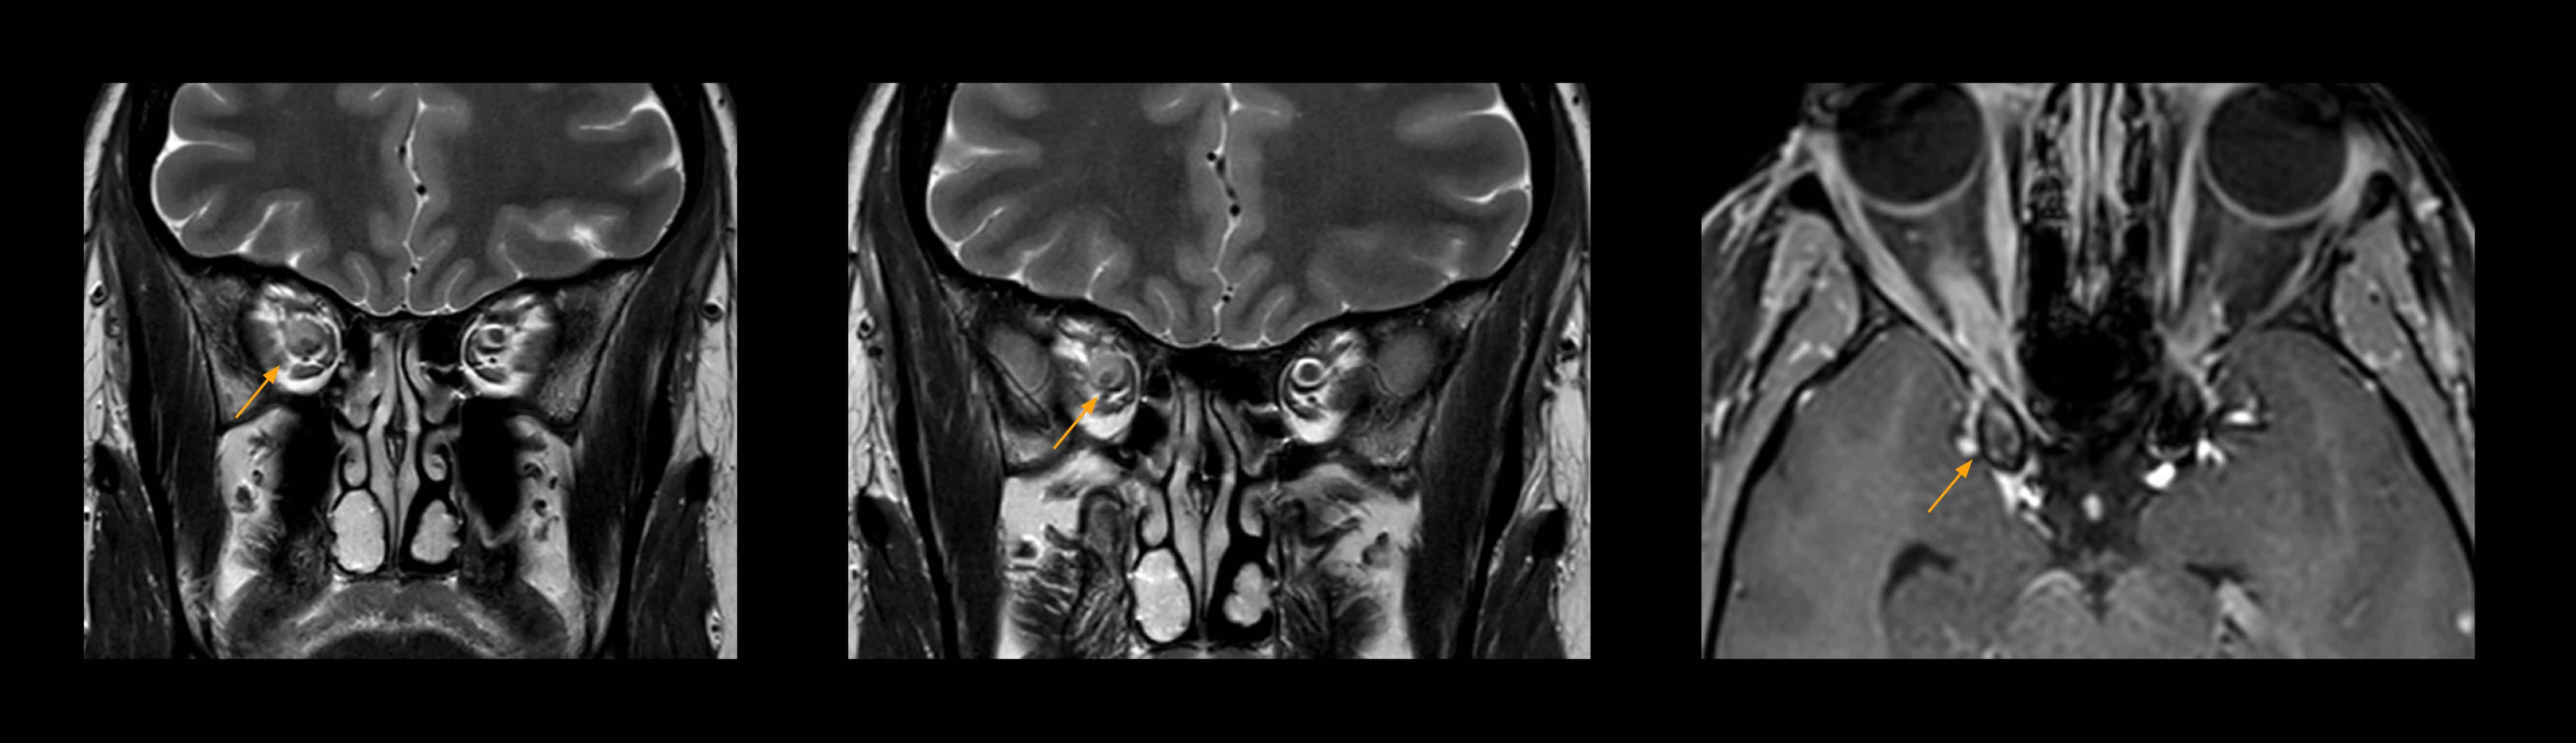

In select cases, the MR 7700 has helped the hospital’s physicians more clearly visualize pathology. “We’re definitely getting the impression that tumors are better delineated with the MR7700,” Dr. Heindel says. “For example, I examined a patient who had been diagnosed in another hospital with possible neuritis of the optic nerve. However, the MR 7700 images allowed me to diagnose it as an optic nerve sheath meningioma, a rare and often misdiagnosed, slowly growing tumor that wascausing the visual disturbances in the patient. The lesion was so well delineated on the high resolution MR 7700 images that our neurosurgeon decided he did not need a biopsy before proceeding directly with decompression of the optic canal and peeling away those tumor cells.”

High-resolution MRI impressively demonstrates the compression and narrowing of the right optic nerve in this case of optic nerve sheath meningioma (ONSM). The coronal T2-weighted images show the hyper-intense, half-moon shaped lesion, that is clearly visible in the axial T1W image after contrast injection (right). These imaging findings were so convincing that there sponsible neurosurgeon did not consider a pretherapeutic histological clarification.

High resolution-MRI impressively demonstrates the compression and narrowing of the right optic nerve in this case of optic nerve sheath meningioma (ONSM). The coronal T2-weighted images show the hyper-intense, half-moon shaped lesion, that is clearly visible in the axial T1W image after contrast injection (right). These imaging findings were so convincing that there sponsible neurosurgeon did not consider a pretherapeutic histological clarification.